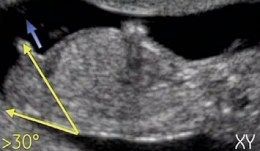

А вот фото, которые я нашла на просторах интернета с "инструкцией" на мальчика

у мальчика половой бугорок со спинкой образуют угол в 30 градусов

У девочек Угол со спинкой меньше 30 градусов

Все фото-примеры как раз рассказывают про определение пола на 13-ой недельке